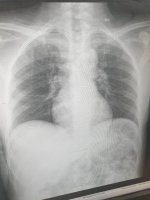

اشعر منذ ٦ ايام بألم شديد في البول و بعد ذلك ألم في الجانب الأيسر و منذ ٤ ايام بدأت درجة حرارة جسمي ترتفع ال ٣٨ و حتي الان مع العلم ان الألم في الجانب الأيسر، أمس ابنتي الصغيرة شعرت بارتفاع في درجة الحرارة و صداع أخذها إلي الطبيب قاله أنها مريضة لكورونا الدرجة الرابعة .. فذهبت انا إلي المستشفى لأني احسست اني انا الاخره مريضة كورونا ، فاقمت بعمل تحليل دم كامل و صورة للأشعة أبلغني الطبيب أنه لا يري شي غير طبيعي مرفق لكم التحليل الدم الكامل و للأشعة

التحاليل ضمن الطبيعي ولا يوجد مايشير لكورونا وقد تكون الاعراض لديك ناتجة عن انتان بولي او حصيات بولية لذا يفضل اجراء تحاليل للبول مع ايكو للجهاز البولي